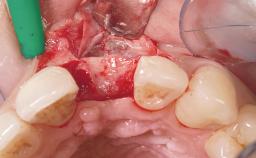

Immediate Flapless Placement of an Implant in a Maxillary Right Lateral Incisor Site

This 43-year-old male patient, a non-smoker, came to our practice because of a fracture of tooth 12 caused by a bicycle accident. Due to the combined para- and infrabony crown and root fracture, tooth extraction, and subsequent implant placement were suggested to the patient as the therapy of choice. The patient had high esthetic expectations with regard to the treatment outcome and asked for an immediate fixed provisional restoration. His individual esthetic risk profile summed up to a medium esthetic risk.

Placement Protocol Immediate implant placement

Loading Protocol Immediate

Provisional Implant-Supported Prosthesis Prosthodontic margin > 3 mm apical to mucosal margin Prosthodontic margin > 3 mm apical to mucosal margin